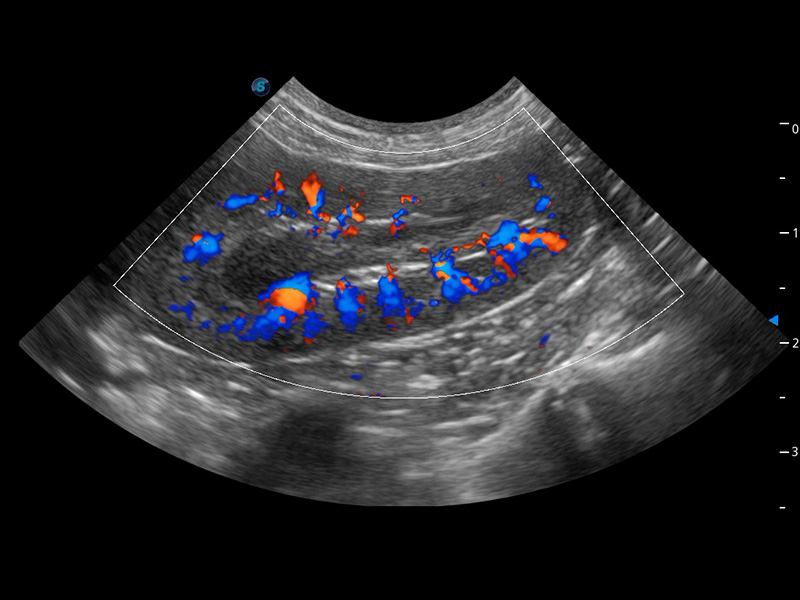

ProPet 60 作為一款高端臺式動物超聲設(shè)備,為動物醫(yī)生的日常診斷提供了一系列貼合動物臨床需求、解決臨床實際問題的高級成像功能。憑借全系列高清探頭,滿足醫(yī)生對腹部、心臟、生殖、淺表、肌骨等成像的所有需求,切實幫助您提升檢查效率,提高診斷信心。